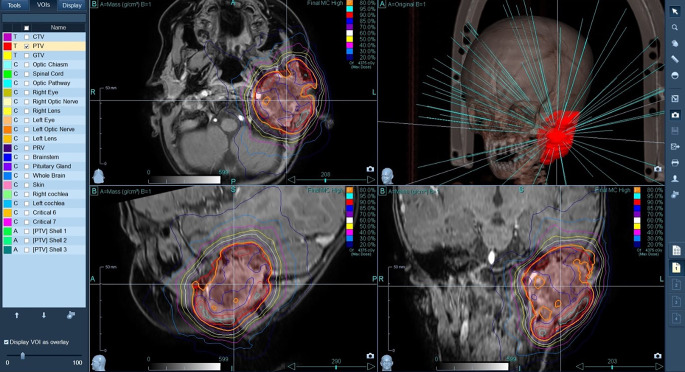

Methods: In our case report, we present a 17-month-old girl with malignant myopericytoma who was successfully treated using CyberKnife (Accuray; Sunnyvale, CA, USA) stereotactic radiotherapy.

Results: A rare localization of the tumor caused significant challenges during the course of treatment. Radical surgical resection was not achievable due to the tumor's location in the inner ear; therefore chemotherapy was initially given to the patient. However, due to the fast progression of the tumor during chemotherapy, we decided to use CyberKnife stereotactic radiosurgery (SRS; 5 fractions of 7 Gy) in order to prevent further invasion of the surrounding tissues. During SRS, tumor growth stopped and the tumor then gradually regressed. Since completion of treatment (currently almost 5 years) our patient has been in complete remission without any significant side effects of the radiation therapy.